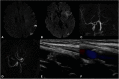

Case presentation: A 60-year-old woman with chronic hypertension rapidly developed right hemiplegia. She had been suffering from slight headache and abnormal sensation in the right limbs 1 week before the ictus. MRI demonstrated small acute infarctions in the left middle cerebral artery (MCA) territory. The left ICA was not visualized on MRA. Diffusion-perfusion mismatch was indicated by the automated image postprocessing system. Endovascular recanalization was planned to prevent the progression of cerebral infarction. After advancing a 5MAX ACE, initial left ICA angiography was performed, resulting in extravasation of contrast medium from the C2 segment of the left ICA. 3D rotational angiography revealed left ICA dissection of the C2 segment. To secure hemostasis, the patient underwent internal trapping at the C1 and C2 segments of the left ICA. Collateral flow to the left MCA via an anterior communicating artery was observed. On day 28, the patient was transferred to a rehabilitation hospital with right hemiplegia and motor aphasia.